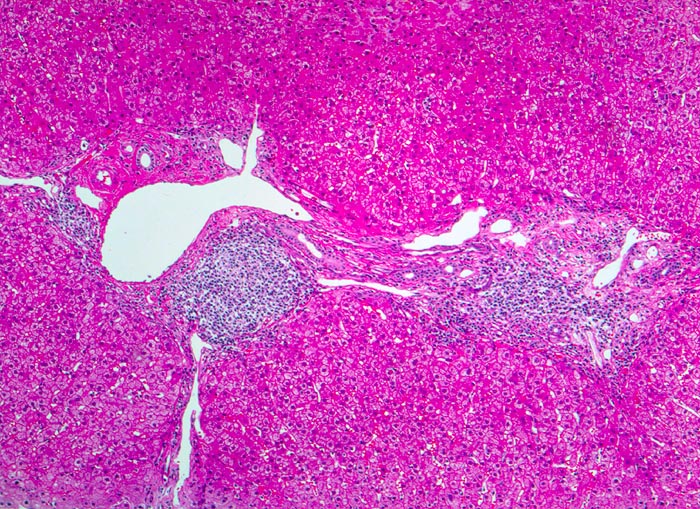

• Dichte mononukleäre portale und lobuläre Entzündungsinfiltrate mit Ausbildung von Lymphfollikeln in den Portalfeldern.

• Übergreifen der Entzündung auf das Parenchym (=Interface oder Grenzzonenhepatitis).

• Geringe Portalfeldfibrose. Das sollte der Kliniker dem Pathologen mitteilen: